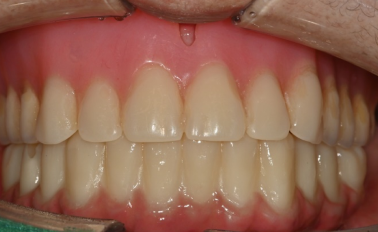

반갑습니다, 하루임플치과입니다. “앞니가 다 썩었어요.” “이가 빠진 지 오래됐고, 남아 있는 앞니도 흔들려요.” 이렇게 말씀하시며 내원하시는 분들이 종종 계십니다. ...

치과에 오시는 많은 분들이 “이 치아는 빼야 하나요?” “임플란트를 해야 한다고 하던데 맞나요?” 라는 고민을 가지고 계십니다. 특히 앞니처럼 심미성·...